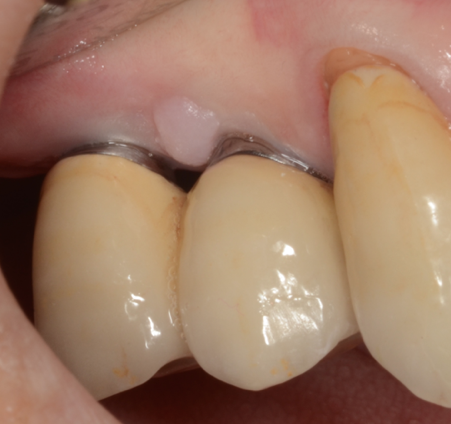

The contours of the prosthesis can have a significant impact on the patient’s ability to maintain good oral hygiene at home and keeping healthy peri-implant tissues. The practitioner should be aware of this issue and make sure restorations are as cleansable as possible. For example, a concave surface from the abutment to the buccal surface is a plaque trap and should be immediately corrected (Figure 5 and Figure 6).

Concavity in the buccal surface of the prosthesis design. The resultant imperfect fit creates a “trap” for plaque.

Figure 5

Figure 6